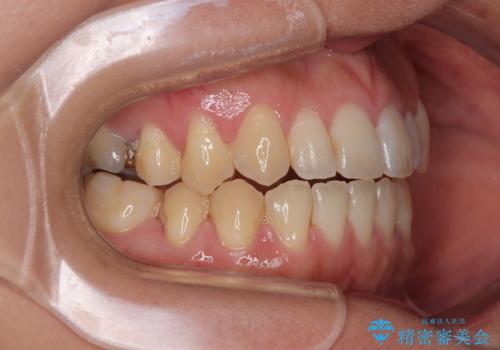

【モニター】食事が取りづらい 極端な開咬をインビザラインで解決

- 極端な開咬を気にして来院された患者様です。

開咬の方の特徴として、幼少期の指しゃぶりの癖や、強い舌の突出癖が挙げられます。

こちらの患者様も強い舌の突出癖が認められたため、矯正治療を行うにあたり、舌のトレーニングをしっかりと行っていただくように指示をいたしました。

開咬はインビザラインが得意とする歯列不正であるため、舌のトレーニングを行いながら、インビザラインにて矯正治療を行うこととしました。

担当医としては、もっと上下の前歯を接触させるところまで治療を進めたいという思いがありますが、今まで咀嚼できなかったものが食べられるようになったということで、この状態で治療終了となりました。